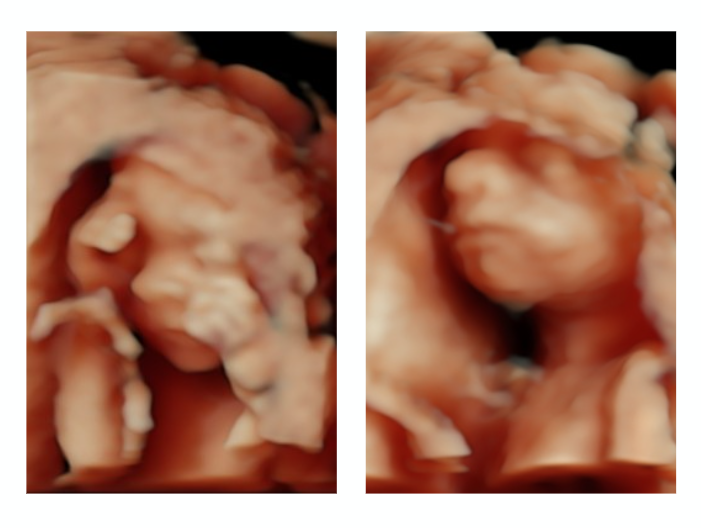

Image Description: Face only

Between 26 - 32 weeks gestation is the best time to view your baby’s facial features. At this stage of pregnancy your baby is usually sitting in a good position with enough surrounding fluid to capture those beautiful detailed images of the eyes, nose, lips and even ears.